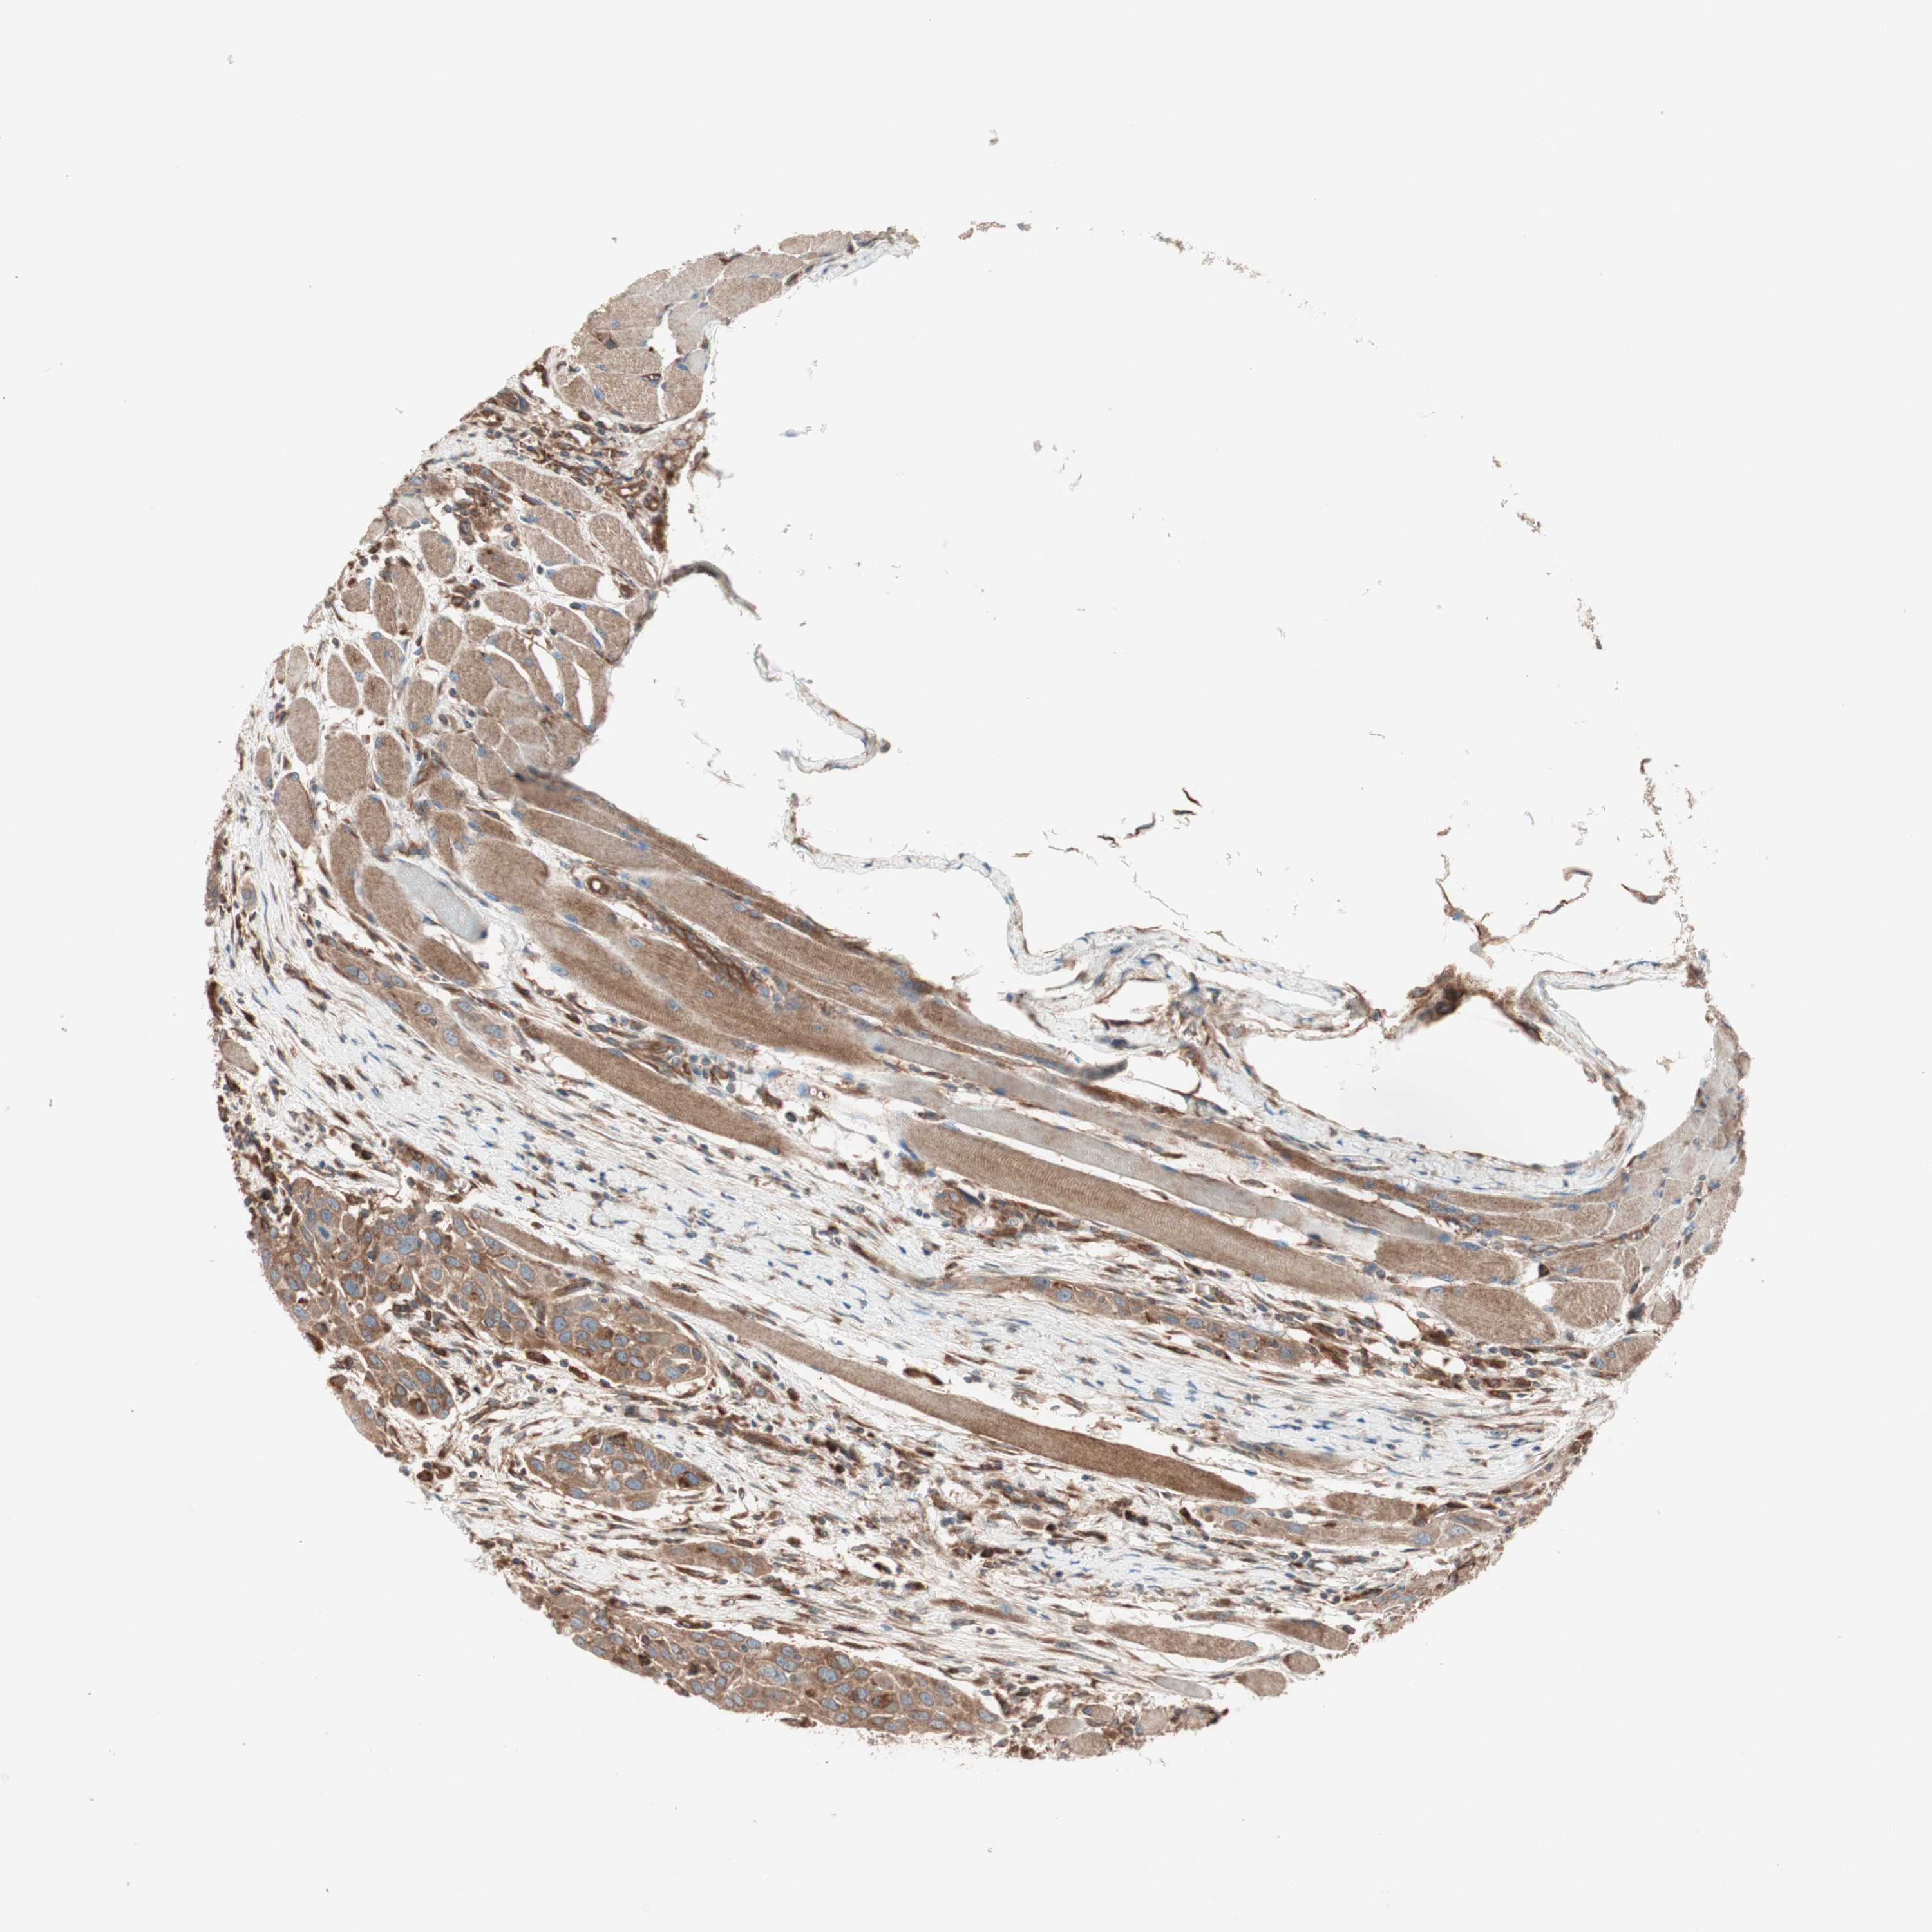

HEAD AND NECK CANCER - Protein expressioni

A mouse-over function shows sample information and annotation data. Click on an image to view it in a full screen mode. Samples can be filtered based on level of antibody staining by selecting one or several of the following categories: high, medium, low and not detected. The assay and annotation is described here.

Antibody stainingi

Antibody staining in the annotated cell types in the current human tissue is reported as not detected, low, medium, or high, based on conventional immunohistochemistry profiling in selected tissues. This score is based on the combination of the staining intensity and fraction of stained cells.

Each image is clickable and will lead to virtual microscopy that enables deeper exploration of all samples and also displays staining intensity scores, fraction scores and subcellular localization as well as patient and tissue information for each sample.

Antibody HPA049354

Antibody CAB004567

Staining

High

Medium

Low

Not detected

Intensity

Strong

Moderate

Weak

Negative

Quantity

>75%

75%-25%

<25%

None

Location

Nuclear

Cytoplasmic/membranous

Cytoplasmic/membranous,nuclear

Adenocarcinoma, NOS